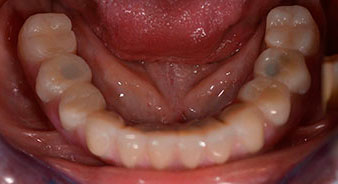

La paciente de 64 años se presentó con una dentición residual compuesta por las piezas dentales 38, 33 y 43 en el maxilar inferior y con una prótesis temporal fijada con ganchos en el maxilar inferior (figs. 1 y 2).

Tras explicarle las distintas opciones de tratamiento, la paciente se decidió por la extracción de la dentición residual en el maxilar inferior, la implantación inmediata y el tratamiento con el método Fast & Fixed (bredent medical), con el que la prótesis dental fijada provisionalmente se atornilla sobre cuatro implantes en el mismo día de la intervención. El objetivo era operar a la paciente el viernes para que el lunes pudiera tomar parte en los exámenes orales para la prueba de acceso a la universidad.

Para la planificación y la minimización del riesgo, se realizó una tomografía volumétrica tridimensional (TVD, Planmeca) que mostró que la calidad y la cantidad del tejido óseo era suficiente para la intervención quirúrgica y el tratamiento inmediato con el método Fast & Fixed. Siguiendo el protocolo de este método, se insertaron los implantes en la región de las piezas 35, 32, 42 y 45. Debido a la inclinación de hasta 45 grados de los implantes distales, el perfil de emergencia se desplazó hacia posterior y se generó un mayor polígono de soporte (fig. 3).